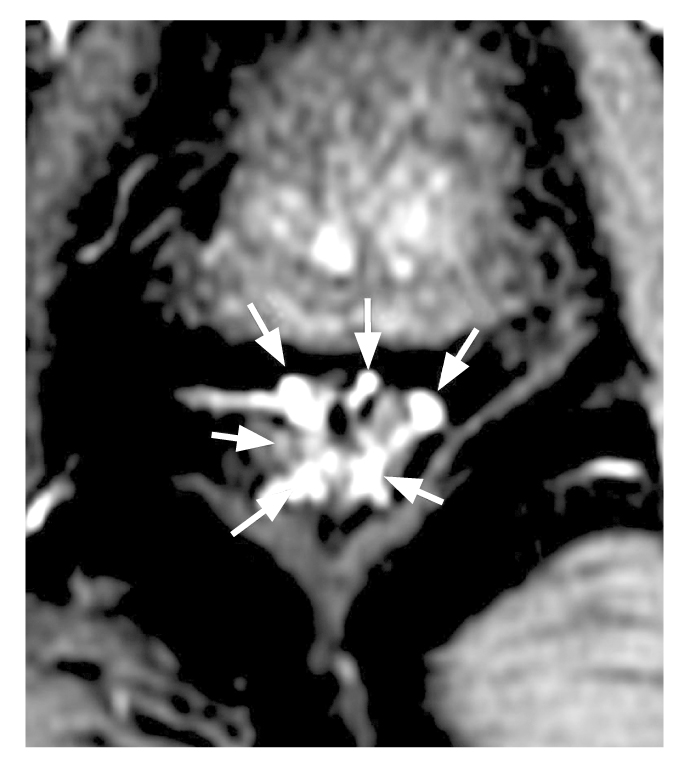

Следует отметить, что в 1/3 (34%) случаев определялось по 2 ветви верхней прямокишечной артерии с последующей трифуркацией, причём задние ветви отходили в виде дуг к задней стенке кишки на 5 и 7 часах условного циферблата — вариант 2. На рис. 6 изображены первый и второй варианты. Так же редко, всего в 2 наблюдениях, отмечалась сосудистая аркада в виде дуги, питающая почти всю окружность кишки по типу кровоснабжения тонкого кишечника — вариант 3 (рис. 7). Чуть более часто, в 6 случаях, наблюдался рассыпной тип с одновременным или последовательным отхождением от верхней прямокишечной артерии 6 отдельных ветвей к стенке кишки — вариант 4 (рис. 8). В 4% случаев наблюдалось по 4 ветви верхней прямокишечной артерии, 2 из которых формировали бифуркации, а 2 шли отдельно — вариант 7.

Рис. 8. Шесть терминальных ветвей верхней прямокишечной артерии до погружения в стенку кишки.